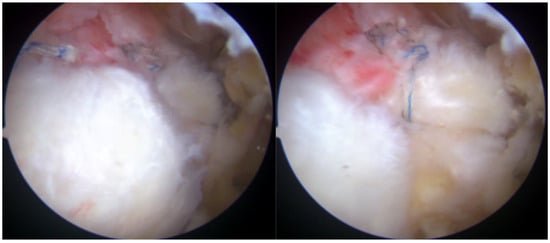

On physical examination, clinical findings included positive impingement signs, weakness in shoulder abduction and external rotation, restricted range of motion, and tenderness to palpation over the lateral aspect of the right shoulder, corresponding to the anatomical location of the rotator cuff tendons. Magnetic resonance imaging (MRI) corroborated these findings, revealing a full-thickness tear involving the supraspinatus and infraspinatus tendons (Figure 1).

Figure 1.

Preoperative MRI showing full-thickness rotator cuff tear.

Taking a closer look at preoperative MR images, it is possible to glimpse the line of the tear, which is oblique, and the two sheets of the tendon, which have different degrees of retraction (Figure 12).

Figure 12.

Preoperative MRI with identification of the line of the tear and the two separated sheets of the supraspinatus tendon, with different retraction.

Preoperative magnetic resonance imaging can reveal the orientation of the tear, and the varying degrees of retraction in the tendon sheets. However, while imaging provides insight into tendon retraction, it does not yield information about the elasticity of the tissue, which can only be accurately assessed during an arthroscopic examination. Arthroscopy in the presented case revealed the separation of sheets 2 and 3 within both the infraspinatus and supraspinatus tendons. Both sheets of the infraspinatus tendon were deemed repairable, while sheet 2 of the supraspinatus tendon could not be adequately repositioned. Consequently, following the rotator cuff repair, a defect remained in the supraspinatus tendon, which the senior Author opted to address with the application of a Regeneten implant.